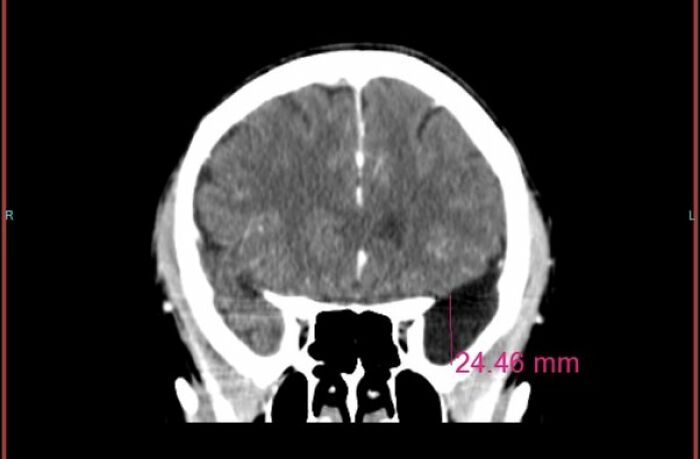

I was going to the VA for sinus infections and headaches. With the recent passing of the PACT ACT I figured I could potentially get a 30% disability rating or about a $300 monthly check. They sent me for a CT scan. I was there late on a Friday. They wouldn’t let me leave without talking too a doctor. Well all the doctors had left already. The nures walked me out. She told me schedule a mri. Not to drop everything but schedule it soon. A few weeks later I had an mri. The VA called me a week later and told me they were referring me to a neurosurgeon. I asked what for. They said I had a bone lesion. A few weeks later I went to see the neurosurgeon. I had researched bone lesions and figured he would tell me to have an mri every 6 months to keep an eye on it. Didn’t have my wife come as it was going to be a nothing appointment. I had scheduled to go checkout a car forsale afterwards.

the neurosurgeon tells me I have to have surgery. I ask why. He said to remove the tumor. I am confused, how is this a brain tumor? I ask to see pictures of what he is talking about. Here is what he showed me. The tumor had eaten away my skull.

Well, walking out of the hospital without losing it was the 2nd most difficult thing I have ever done. The most difficult was calling my wife and telling her. We scheduled my surgery for 3 weeks later.

The VA denied my benefits for sinus issues so no money. But they did pay for the whole surgery, $150k.

it has a happy ending. All good and playing volleyball and golf again. I am one lucky sob. I never had any symptoms and would have had no idea until it was too late. It was benign.